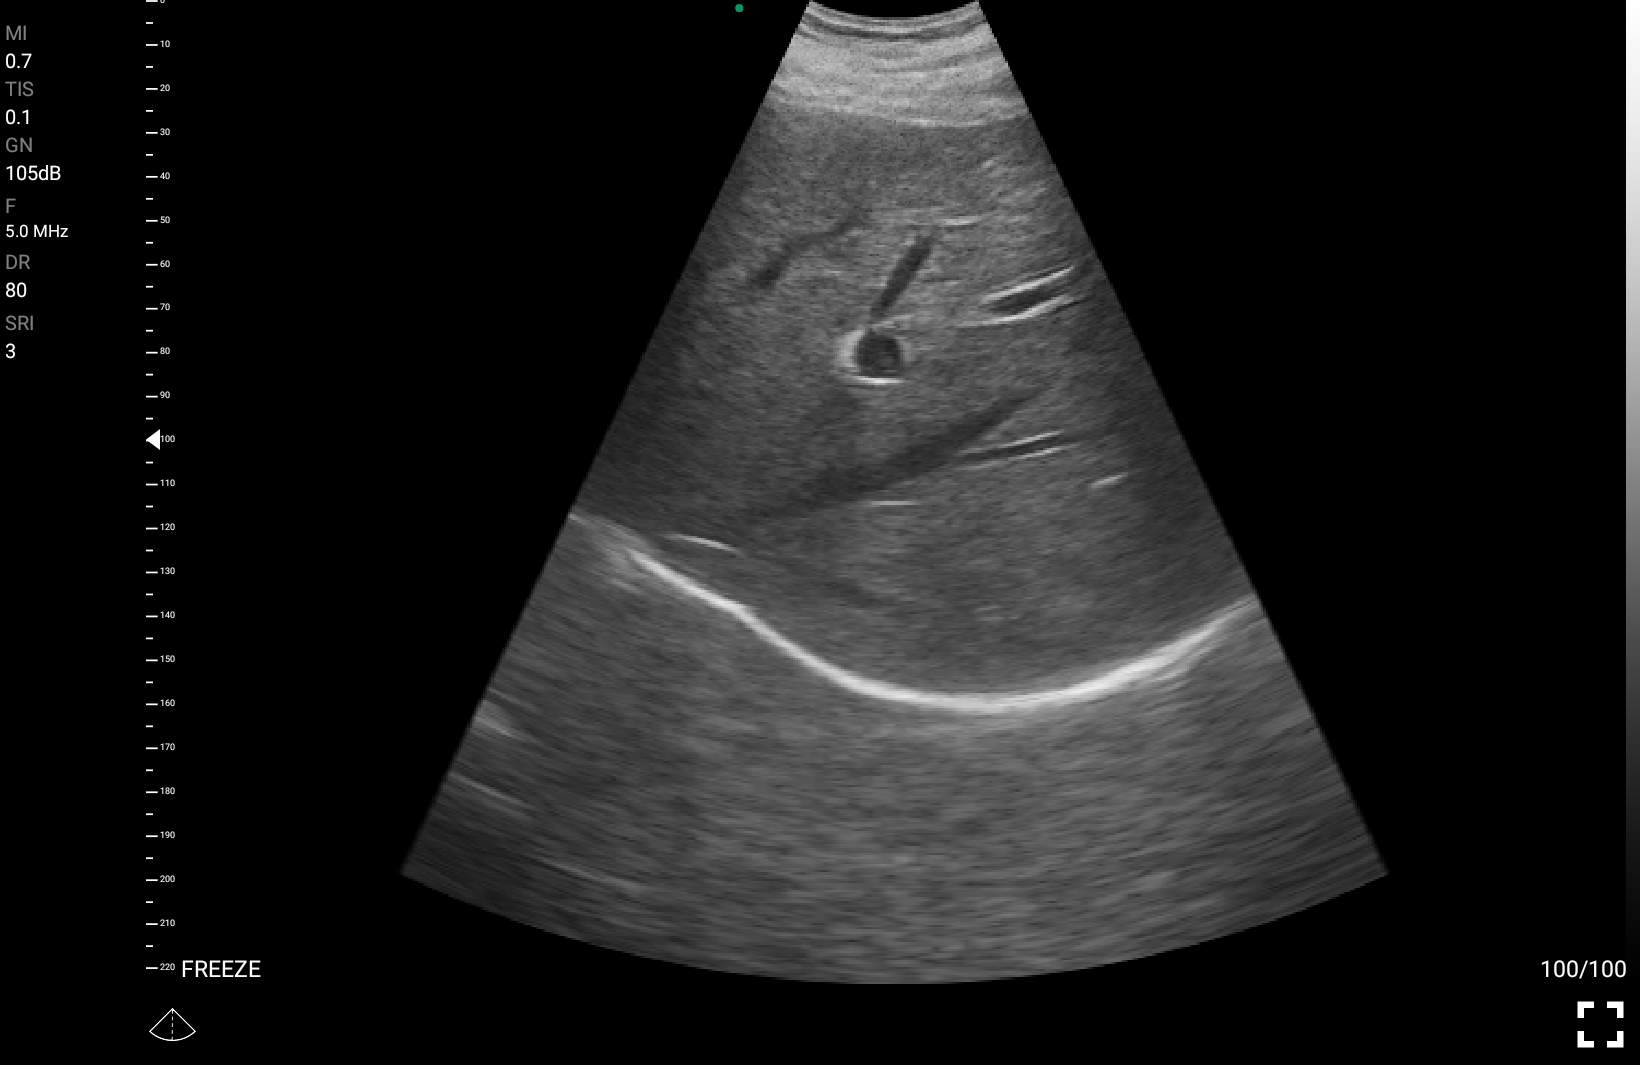

• Θλάσεις και αιμορραγίες: Η υπερηχογραφία μπορεί να χρησιμοποιηθεί για την άμεση εκτίμηση εσωτερικών τραυματισμών, εντοπίζοντας αιμορραγία ή θλάση σε περίπτωση τραύματος ή επείγουσας κατάστασης.

• Ανίχνευση αιματώματος ή αγγειακών διαταραχών σε ασθενείς που παρουσιάζουν οξείες καταστάσεις που μπορεί να απαιτούν άμεση επεμβατική θεραπεία.

Παραδείγματα

Ολες οι παραπάνω απεικονιστικές εξετάσεις έχουν ληφθεί από φορητή συσκευή όπως: Apple Iphone, Tablet, Samsung Mobile Phones και διάφορες άλλες φορητές συσκευές.